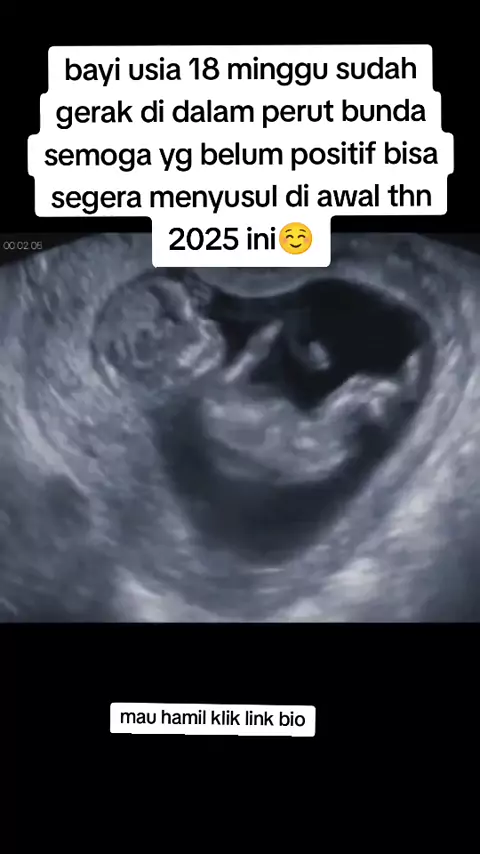

Amiiin🥺Untuk konsultasi bisa via wa ya bunda#pejuanggarisdua#promilcepathamil